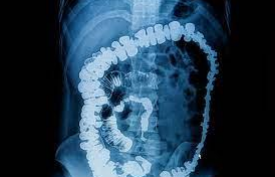

En 1910, se introdujo el sulfato de barrio, que permitió estudios del sistema gastrointestinal. Uno de los primeros investigadores en el campo de las imágenes gastrointestinales fue Walter Cannon, un fisiólogo de Harvard que realizó estudios en el estómago con sales de bismuto.

• Aplicaciones desde 1895 hasta nuestros días de la radiación ionizante

Aplicaciones desde 1895 hasta nuestros días de la radiación ionizante